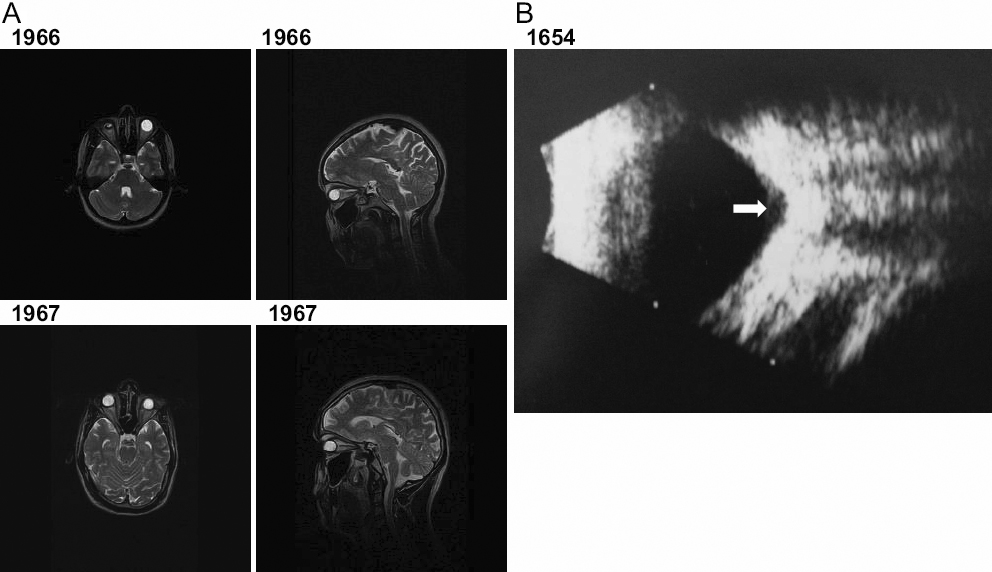

Figure 4. Retrospective analysis of the patients with sclerocornea for further ocular abnormalities. A: Axial and sagittal T2-weighted MRI scans of the head and orbits of two affected members 1966 and 1967 (aged 25 and 22 years

old) from the MEP54 pedigree. Both patients demonstrate aphakia as depicted by the absence of a dark lens in the anterior

part of the eye. In the absence of surgery, the left eye of patient 1966 seems to be phthisical. The axial lengths for 1966

are 10 and 17 mm and 1967 are 19 and 16 mm for the right and left eyes, respectively confirming that there is also microphthalmia.

The sagittal section shows that there are no obvious structural abnormalities of the brain. B: Left eye ultrasound scan of patient 1654 from the Mexican pedigree showing an optic disc coloboma (white arrow).